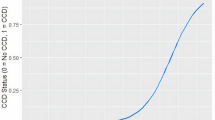

In dogs, as shown in Fig. 5.1, Aβ accumulates in the cortex with a relatively well-described pattern that parallels observations in the human brain (Braak and Braak 1991; Braak et al. 1993; Giaccone et al. 1990; Head et al. 2000; Ishihara et al. 1991; Selkoe et al. 1987; Thal et al. 2002; Wisniewski et al. 1970, 1990). Aβ deposition occurs earliest in the prefrontal cortex of the dog and later in the temporal and occipital cortex (Head et al. 2000), similar to previous reports in humans (Thal et al., 2002). Further, several groups have characterized the age-dependent maturation of Aβ deposits within the canine cortex into several phases (Satou et al. 1997; Schutt et al. 2016). Importantly, the extent of Aβ plaque deposition in the dog brain is linked to the severity of cognitive deficits (Colle et al. 2000; Cummings et al. 1996; Head et al. 1998; Rofina et al. 2006). Interestingly, not all studies show a correlation between Aβ and the presence of canine cognitive dysfunction (CCD) (Chambers et al. 2011; Ozawa et al. 2016). However, studies that show a link between the extent of Aβ and cognition also indicate that the location of the deposition is important. For example, dogs with reversal learning deficits indicative of executive dysfunction tend to show more extensive Aβ deposition in the prefrontal cortex (Cummings et al. 1996; Head et al. 1998). In contrast, poor size discrimination learning ability is associated with large amounts of Aβ in the entorhinal cortex (Head et al. 1998). Soluble Aβ can also be measured in the cerebrospinal fluid (CSF) of dogs, making it a useful marker for aging and cognition intervention studies (Head et al. 2010; Sarasa et al. 2013). The ratio of Aβ42/Aβ40 in the CSF is a good predictor of the extent of Aβ measured biochemically in the brain and also declines linearly with age (Head et al. 2010).

A frequent pathology detected in both normal human brain aging and particularly in AD is the presence of cerebral amyloid angiopathy (CAA), which is described as the accumulation of Aβ in the walls of cerebral vessels (Attems 2005; Attems et al. 2005; Herzig et al. 2006). Aged dogs are also vulnerable to vascular pathology with perivascular abnormalities; CAA is observed frequently in aged dogs (Giaccone et al. 1990; Ishihara et al. 1991; Shimada et al. 1992; Uchida et al. 1990, 1991, 1992, 1993, 1997; Yoshino et al. 1996). The consequences of CAA accumulating in the brains of aging dogs may be a compromise to the function of the blood-brain barrier and impaired vascular function (Prior et al. 1996). In turn, vascular dysfunction and BBB disruptions may lead to microhemorrhages (Deane and Zlokovic 2007; Uchida et al. 1990, 1991). The distribution of CAA in dog brain is similar to humans, with particular vulnerability in the occipital cortex (Attems et al. 2005). However, in a systematic study of the extent of CAA in cognitively characterized pet dogs, CAA increased with age but did not correlate with cognition (Ozawa et al. 2016). Thus, aged dogs develop cerebrovascular abnormalities that may not contribute to cognitive decline but are otherwise consistent with those reported in humans.

Neuroinflammation in the aged human and AD brain may lead to the exacerbation of cognitive decline or potentially mediate other neuropathological events causing dementia (Heneka et al. 2015; Wilcock 2013). Although not as well characterized as neuroinflammation in the human brain, there are several small studies in aged pet dog brains. In a recent study, Schutt and colleagues (Schutt et al. 2016) measured canine cytokines in the prefrontal cortex of 15 aged dogs as compared with 2 young dogs. Pro-inflammatory cytokines were generally at low levels and were not associated with the extent of cognitive dysfunction. However, using measures of glial activation (microglial cells and astrocytes), increasing numbers of both types of cells were associated with more extensive CCD in a study of 37 dogs with various breeds included (Ozawa et al. 2016). Similarly, the level of S100β astrocytosis, a putative measure of inflammation, is also correlated with cognitive deficits in pet dogs (Pugliese et al. 2006).

White matter degeneration can contribute to cognitive decline in humans (Bartzokis 2004; Gold et al. 2012). In a study of myelin protein levels as a function of age in dogs, Chambers et al. report a loss of prefrontal myelin protein (Chambers et al. 2012) that was also associated with some Aβ deposition in CAA. In another study, the extent of ubiquitin labeling in aging dog brains (n = 37) was associated with CCD and is thought to reflect failures in the protein homeostasis in the synapse or in myelin (Ozawa et al. 2016).